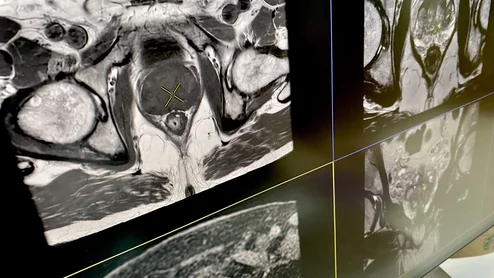

Prenuvo MRI

Sean Clifford filed the lawsuit Sept. 24, 2024, in the New York State Supreme Court, contending a radiologist failed to spot signs of a forthcoming stroke.